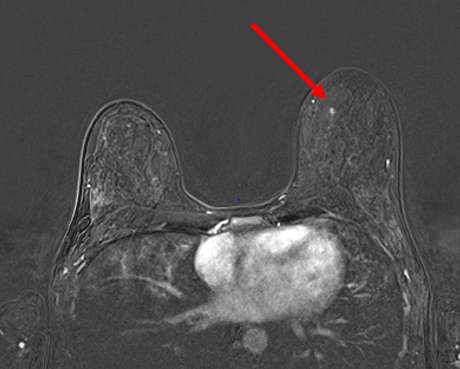

Approximately two-thirds to three-quarters of cancers present as a mass (4). Mass is defined by BI-RADS as a 3-dimensional lesion occupying space within the breast. Similar to mammography and sonography, masses are described by their shape, margins, internal characteristics as well as MRI contrast enhancement pattern (Figure 2).

Figure 2. T1 fat-saturated postcontrast axial subtraction MRI demonstrating enhancing mass in the left breast 11 o’clock. Of note, the left breast saline subpectoral implant is ruptured and collapsed. This mass was demonstrated rapid washout kinetics and assigned BI-RADS 4.

Breast masses are categorized into 3 shapes: oval (including lobulated), round, and irregular. Margins are described as either circumscribed or not circumscribed (including irregular and spiculated margins) (5). Enhancement patterns are described as homogenous, heterogenous, rim enhancement, and dark internal septations. Mass features suspicious for malignancy include irregular size and margin, heterogenous or rim enhancement and washout kinetics (5).